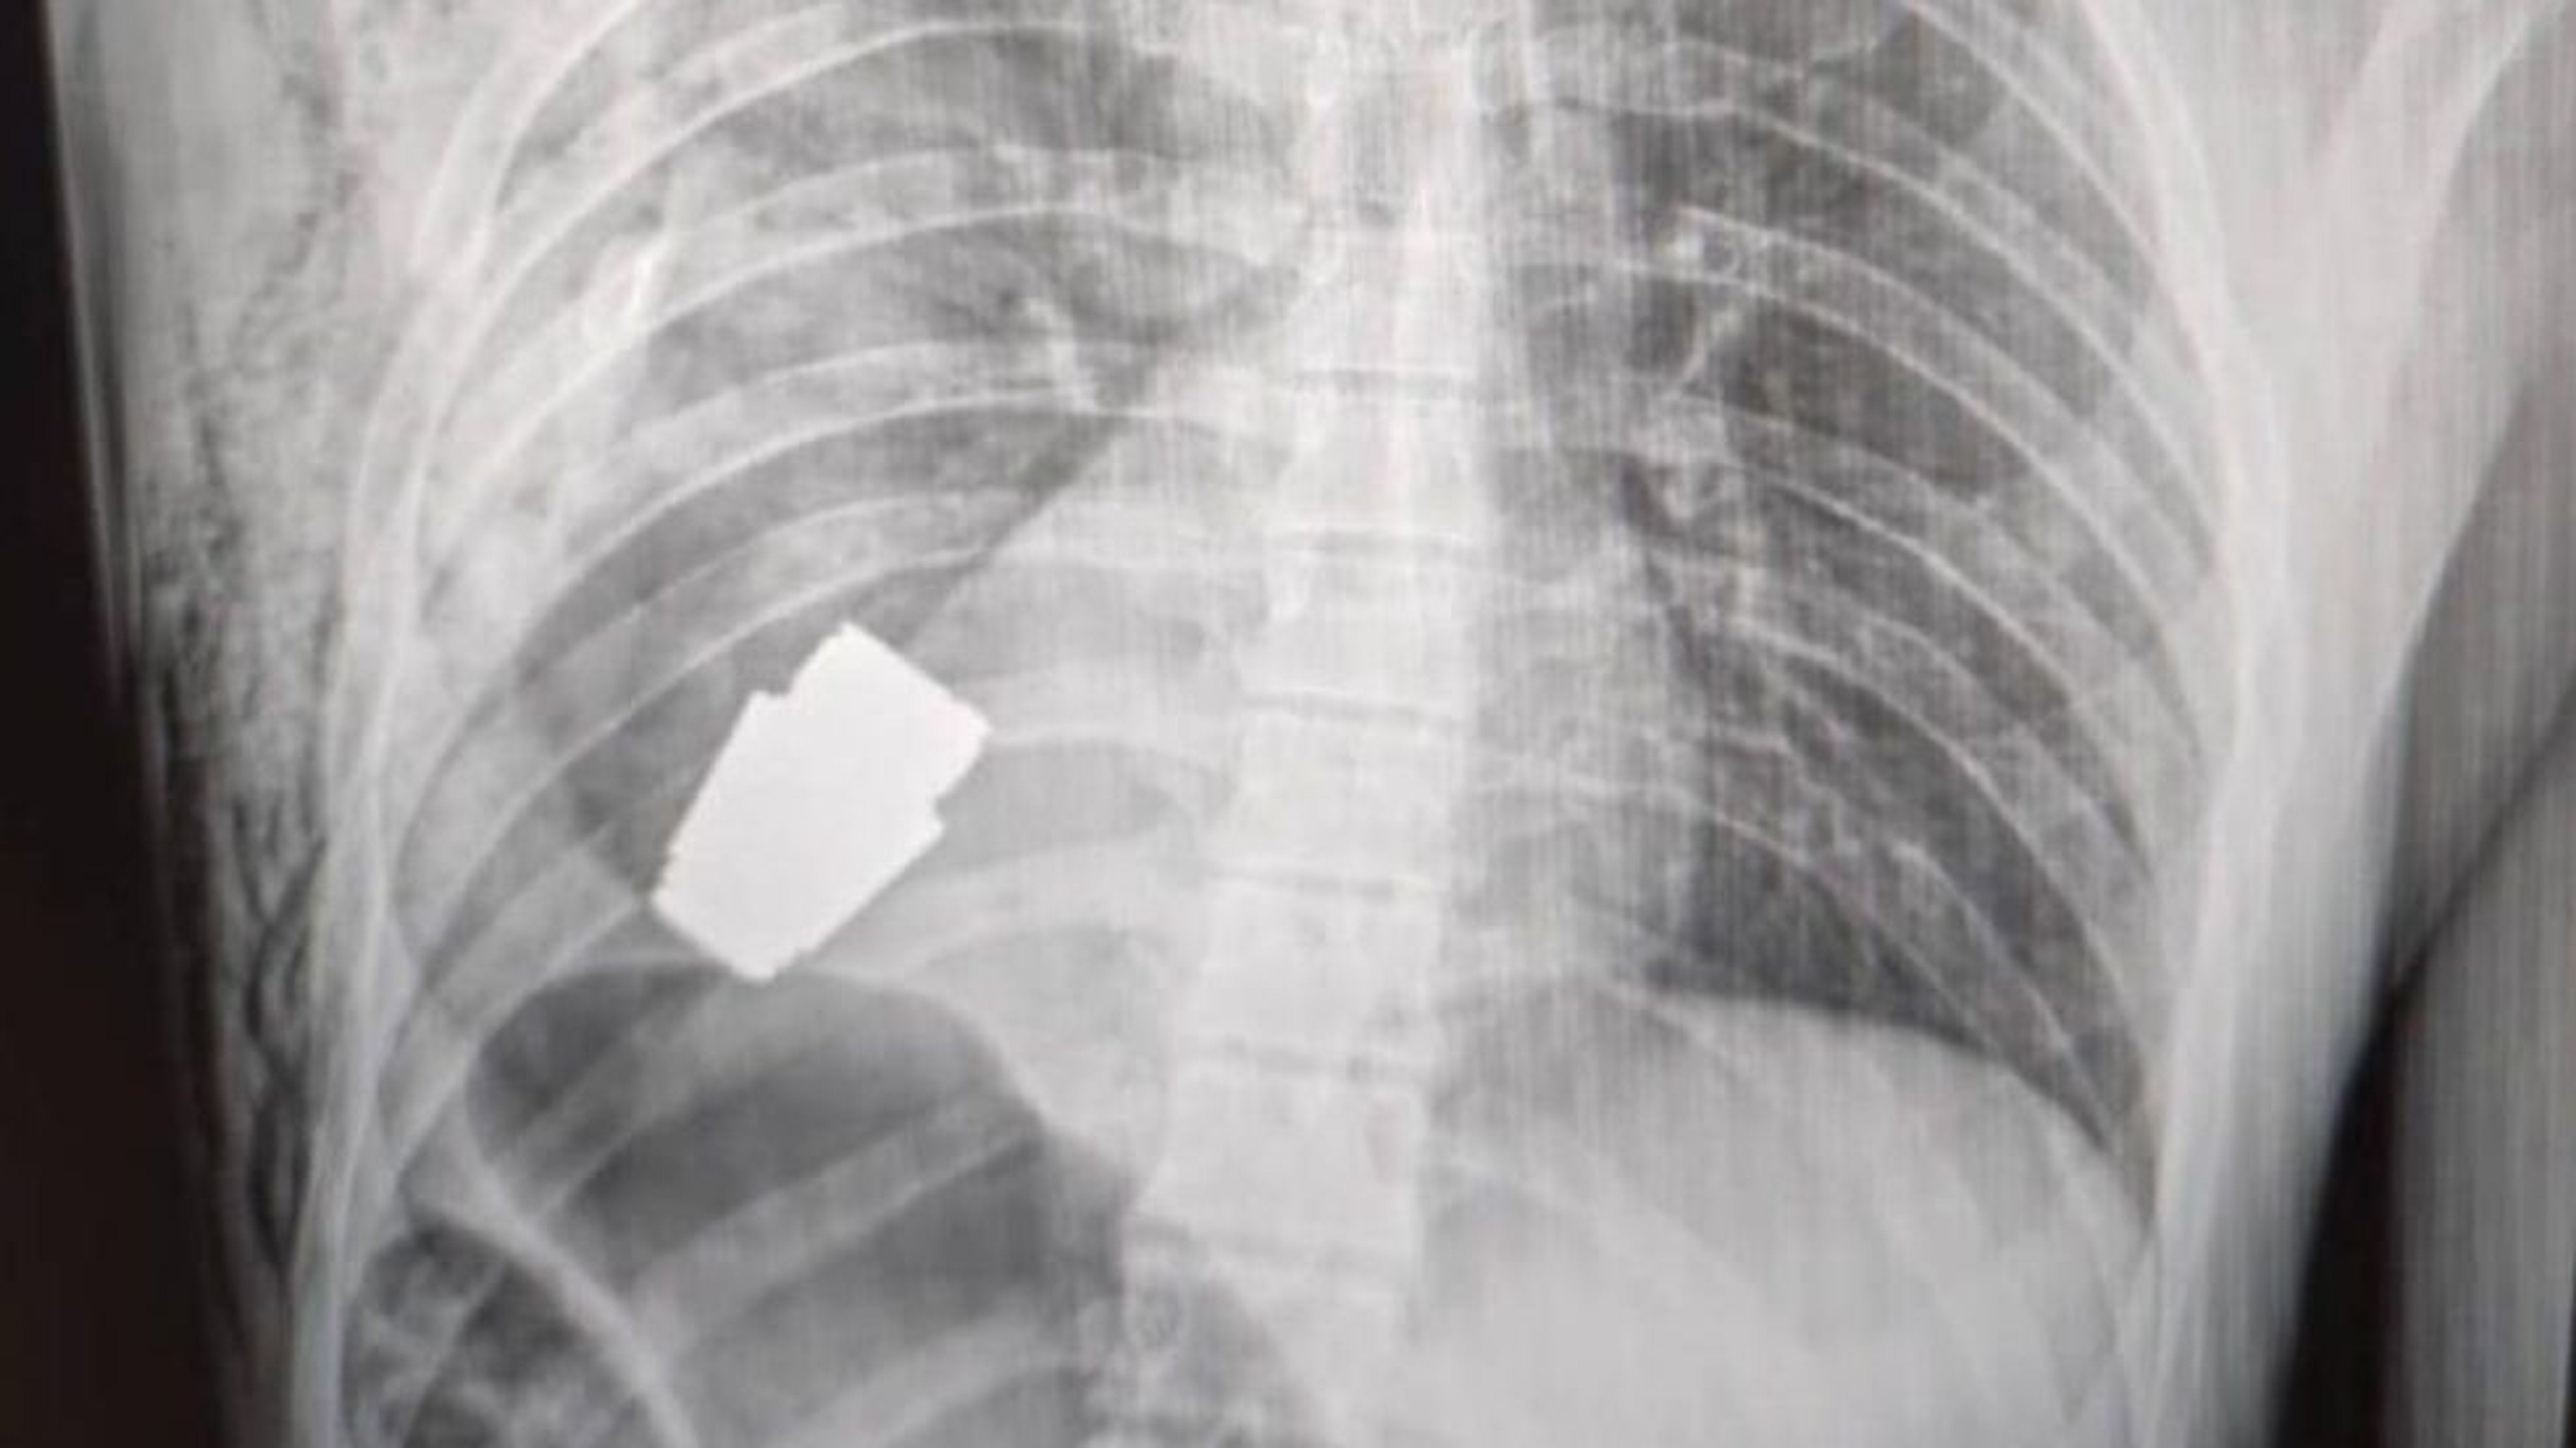

A Ukrainian medical team recently performed a normally unheard-of surgery by removing an unexploded grenade from a soldier’s chest. A Ukrainian Major General of the Medical Service led the group tackling the dangerous surgery. He was accompanied by two sappers, to help mitigate the explosion risk.

The Ukrainian Military Medic’s Facebook page published an x-ray image of the patient and a picture of the Major General. The Facebook post was published last week mentioning the grenade posed such a high explosion risk that they had to perform it without electrocoagulation – a standard practice used to control bleeding with electricity.

The unexploded grenade removed is thought to be a VOG model, fired from a rifle mounted grenade launcher. Munitions of this type have a low failure rate, but several factors could have been at play. Depending on the exact munitions, the arming distance of this type of round may be from 10-40m. Meaning it could have been a point blank shot, or perhaps even a friendly-fire accident. We simply do not know.